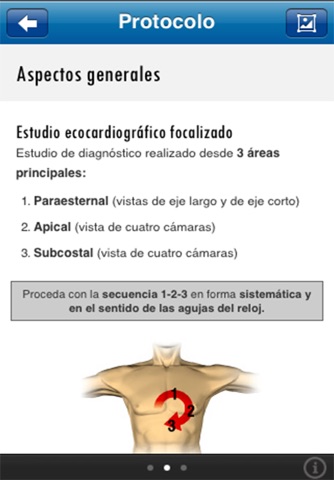

• Resume conceptos clave del examen de Ecocardiografía focalizado (FOCUS)

• Representa las vistas ecocardiográficas FOCUS con animaciones 3D

• Contiene un gran número de vídeos, animaciones de alta resolución, calculadora de rendimiento cardíaco, secciones de evaluación de función ventricular, líquido pericárdico, estado de líquidos, etc.